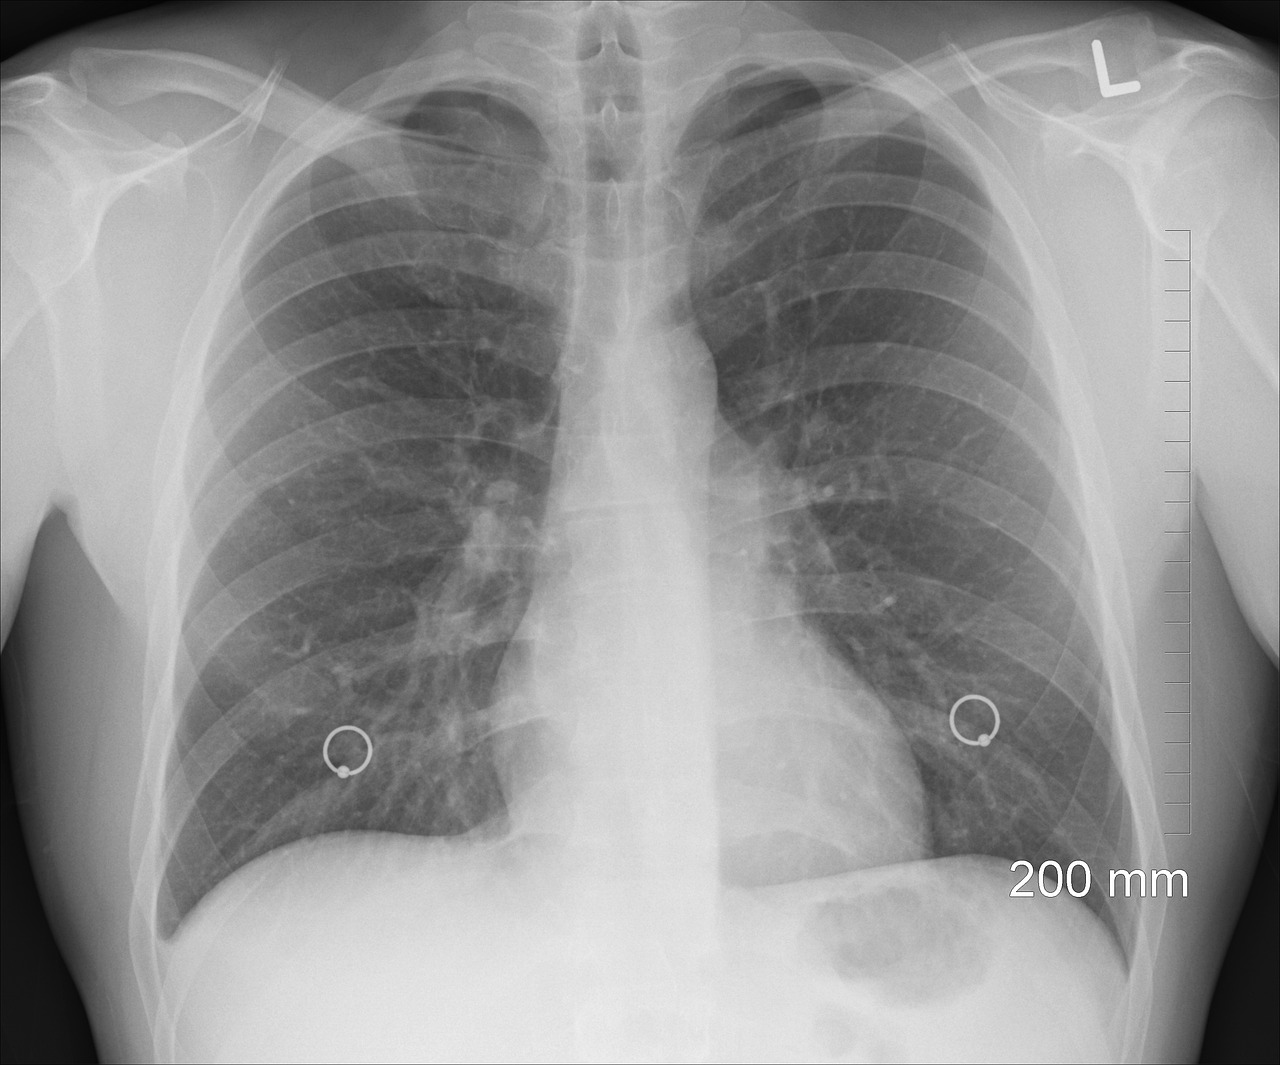

Per la prima volta dopo oltre un quarto di secolo di aumento quasi continuo, la mortalità per tumore del polmone tra le donne dell’Unione europea mostra un segnale che pesa più di tanti slogan: la curva tende a stabilizzarsi. Le stime per il 2026 indicano un valore intorno a 12,5 decessi ogni 100.000 donne, con un calo di circa il 5% rispetto al triennio 2020–2022; nel complesso europeo, la tendenza favorevole riguarda soprattutto le fasce più giovani, mentre oltre i 65 anni l’andamento resta problematico. Lo scenario emerge dallo studio “European cancer mortality predictions for the year 2026”, pubblicato su Annals of Oncology, coordinato dall’Università Statale di Milano con la collaborazione delle Università di Bologna e Parma e con il sostegno di Fondazione AIRC.

Il tumore del polmone rimane la prima causa di morte per cancro nell’UE, in uomini e donne, ma le traiettorie dei due sessi continuano a divergere: tra gli uomini i tassi scendono in modo più marcato, mentre tra le donne — dopo anni di rincorsa — si intravede un punto di svolta. Gli autori collegano questo passaggio alle diverse “storie” del fumo: in diversi Paesi le donne hanno iniziato più tardi rispetto agli uomini e, in alcuni contesti, hanno smesso più tardi, spostando in avanti gli effetti sulla mortalità.